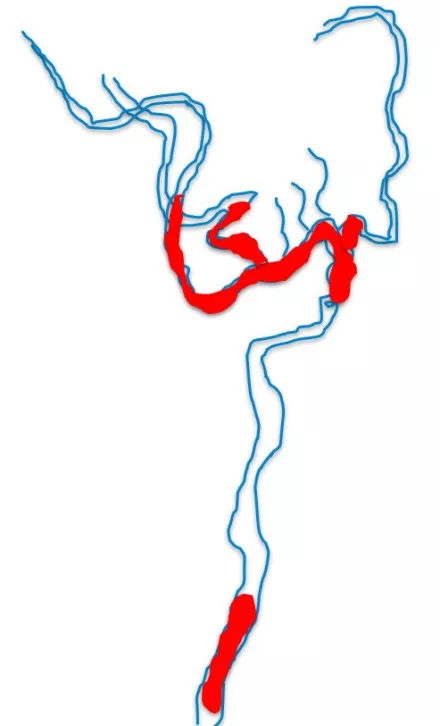

中间导管到位后,因根据平时实践,此时拉栓的成功率非常低,故未行拉栓。再次置入一个微导丝于ACA,微导管置入后冒烟证实于真腔内。之后放置两个支架,MCA中使用6*30mm,ACA中使用4*20mm。

8F指引导管联合6F Navien中间导管,右侧ACA取栓:微导丝到位;Rebar18导管到位,冒烟证实于血管腔内;Solitaire 4-20支架放置ACA-A1分支内

最后双支架联合抽吸拉通血栓。造影提示取栓后血管再通,TICI 3级。

造影提示取栓后血管再通,TICI 3级(A);抽吸联合取出的血栓(B)

➢颈动脉闭塞再通率低的原因:血管弯曲,血栓负荷较大,大血管拉通后,次级血管发生闭塞以及串联病变,都是导致血管再通较差的原因。

➢对于颈动脉高负荷血栓的患者,单支架取栓失败后,双支架取栓是可行的。

➢根据讲者实践经验,直接双支架取栓是安全的。

➢对于栓子负荷大的急性脑梗死患者,双支架取栓可能是一种合理选择。此策略可缩短手术操作时间,减少多次操作后血管内皮损伤,增加血栓捕获能力的优势